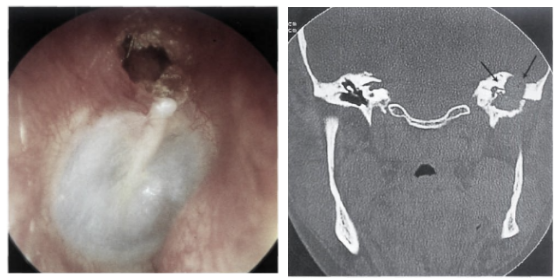

马先生近20多年来右耳反复流脓,右耳听力下降,平时发作时多吃消炎药、用滴耳液滴耳,时好时发。1周前,他又右耳疼痛伴流脓发作,于是在家人陪伴下来我院治疗。耳鼻咽喉头颈外科主任王鑫教授通过详细的耳内镜检查,结合乳突CT,最后,确诊为胆脂瘤型中耳炎,建议手术治疗。随后经过乳突切除、鼓室成形术和抗菌药物等系列治疗,马先生解决了多年的病痛,康复出院了。

那么,什么是胆脂瘤呢?王教授解释,胆脂瘤虽然称为瘤,但与一般的肿瘤是完全不一样的,其实它不是真正的肿瘤。它是因为鼓膜松弛部穿孔,外耳道的上皮细胞长入中耳腔里,由于炎症缠绵不愈,这些上皮细胞活动力增强,层层脱落的皮屑逐渐堆积增大,扩张压迫而侵犯周围骨质,使骨质吸收破坏。拍片时,就会显示出一个“瘤”样的阴影。

因为由于胆脂瘤位置的不同,患者的表现会多种多样,有的很不典型,所以,有长期耳朵流脓、听力下降、耳鸣的慢性中耳炎患者,应及时求助于耳科医师,看是否有胆脂瘤存在的可能。通过耳内镜检查和颞骨CT检查,就可以确诊胆脂瘤性中耳炎。如有胆脂瘤存在,就应及时手术清除,并重建中耳结构。